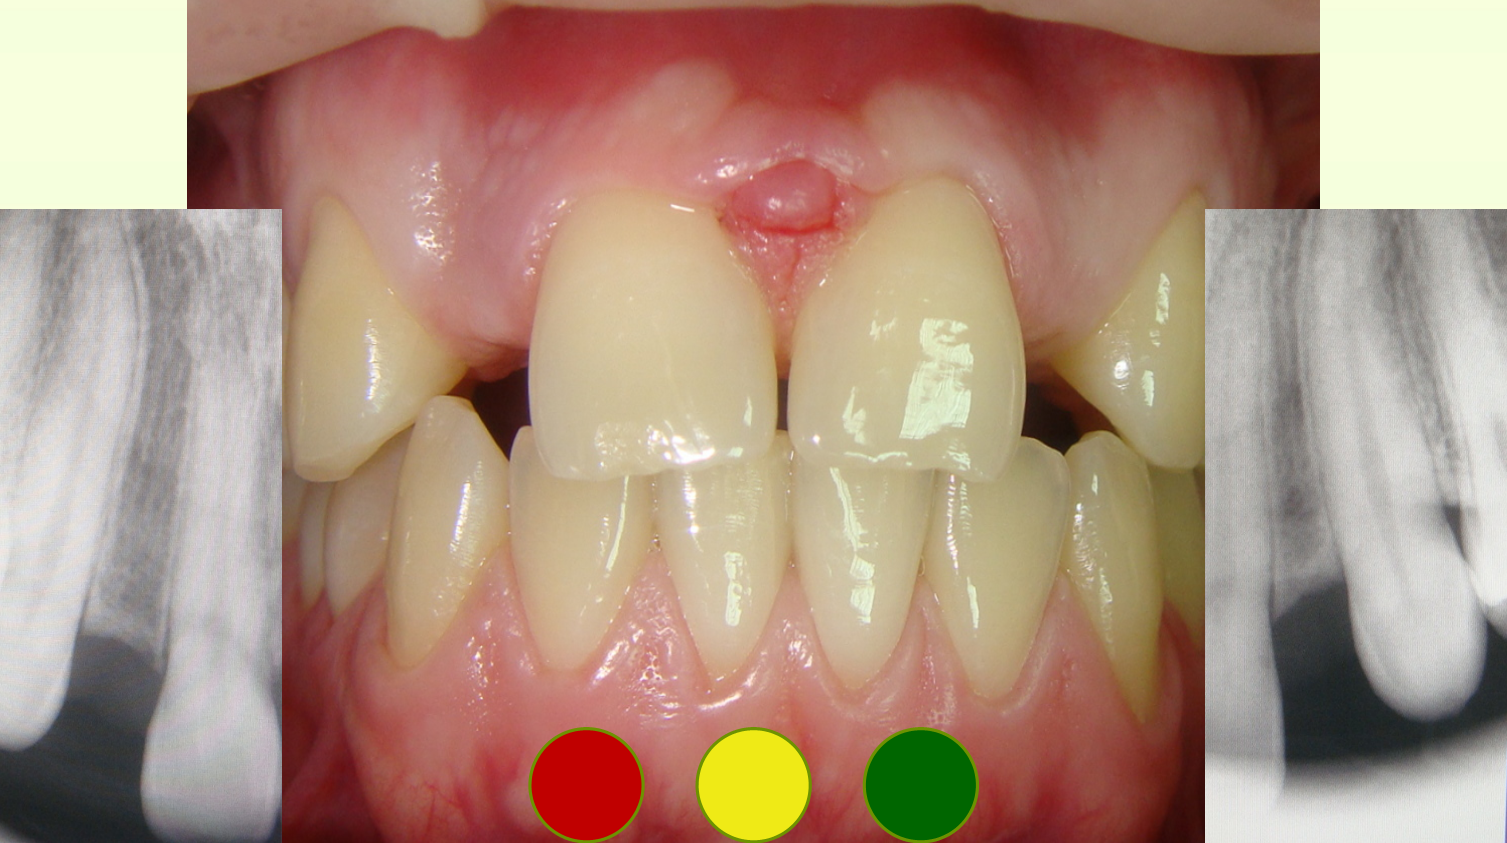

Case 12

“Vector” Implant placement in the area of 22 and 12 missing teeth is the only correct solution.